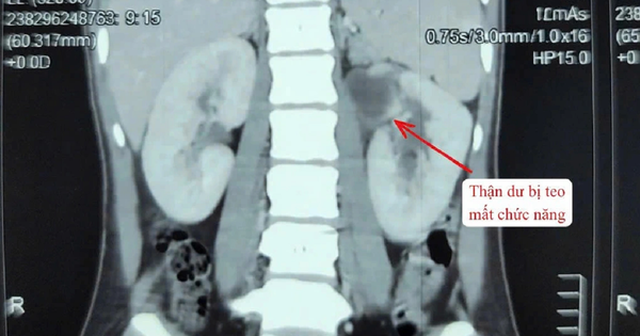

Người bệnh nhập viện trong tình trạng sốt cao, đau vùng hông trái. Qua thăm khám lâm sàng và thực hiện các xét nghiệm cận lâm sàng, các bác sĩ chẩn đoán bệnh nhân mắc dị tật thận - niệu quản đôi bên trái (tổng 3 thận). Trong đó, một thận đã mất chức năng, niệu quản giãn lớn bất thường, chứa nhiều mủ gây nhiễm trùng nặng.

Hình ảnh thận trên phim. Ảnh: BVCC.

Qua thăm khám và thực hiện các cận lâm sàng cần thiết, bác sĩ chẩn đoán bệnh nhân có 2 quả thận bên trái, trong đó một thận bị mất chức năng. Niệu quản đi từ thận mất chức năng giãn to bất thường, chứa đầy mủ gây nhiễm trùng nặng.